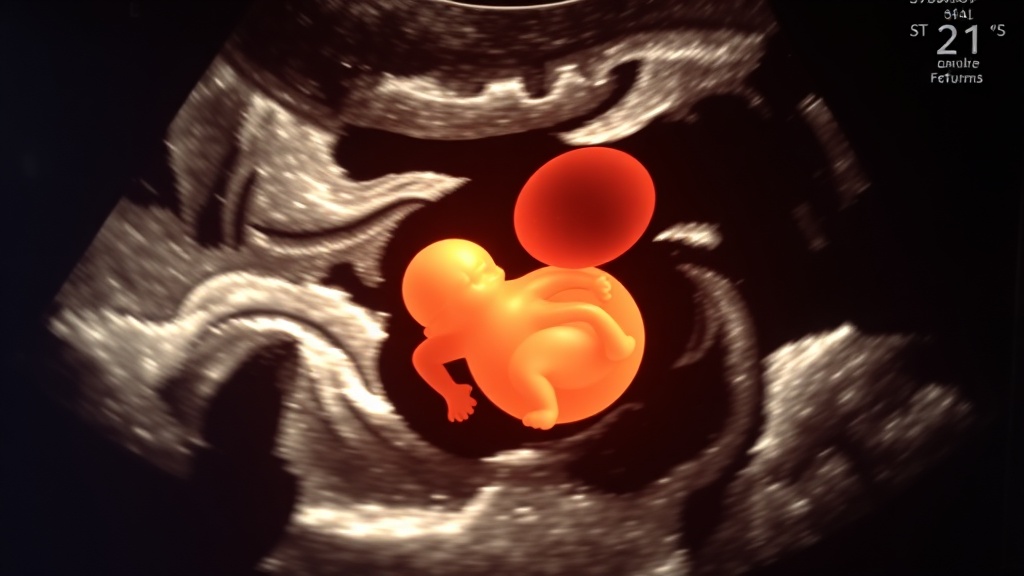

A London woman, Kizzi Woodman, endured a profound tragedy when three private ultrasounds failed to detect severe health problems in her unborn child. She was repeatedly assured her son was healthy during private scans, only to be informed by NHS sonographers at 12 weeks that the baby had serious developmental issues. Sadly, a subsequent NHS scan confirmed the baby had died due to complications, forcing Kizzi to undergo a medically induced miscarriage. This traumatic experience has highlighted concerns within the medical industry regarding the accuracy of private ultrasound services.

NHS sonographers found that Kizzi Woodman's baby had severe health problems, with organs developing outside the body.